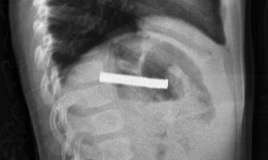

Vərəm – çox ağır infeksion xəstəlikdir. Öskürək xroniki olur, heç bir dərman, türkəçarə saxlamır, uzun müddət davam edir. Metallik səs verir. İlk başda quru ola bilir, sonra yaşa çevrilir. Ən təhlükəli siqnalı bəlğəmdə qan olmasıdır. Xəstə gecələr tərləyir, halsız olur, sürətlə arıqlayır.